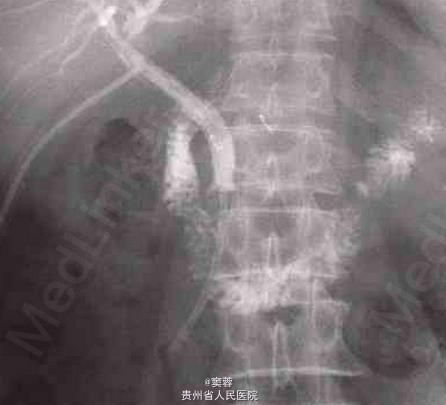

患者男性,60岁,有慢性胆囊炎及胆囊结石病史20年。患者于2006年6月中旬无诱因出现尿黄、皮肤黄,无腹痛、发热等,在当地医院接受经内镜逆行胰胆管造影(ERCP)及胆管塑料支架置入引流。ERCP造影提示患者有肝门部占位。